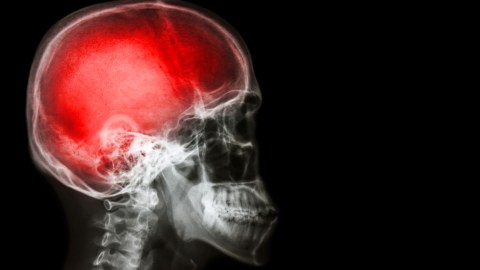

The brain seems to be orderly arranged in ever complex and elegant ways, unique to each individual.

A closer look at the human brain.